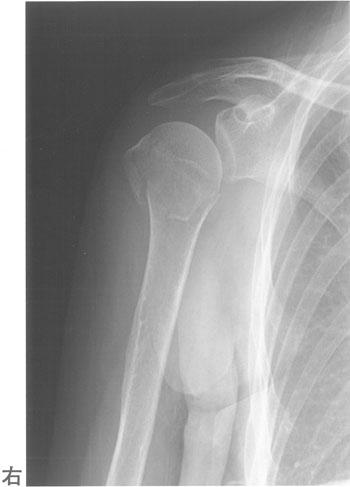

60歳の女性。転倒して右肩関節痛を訴えた。エックス線写真を示す。まず患部に行うべき治療はどれか。

1

ギプス固定

2

極超短波治療

3

三角巾固定

4

髄内釘固定

5

超音波治療